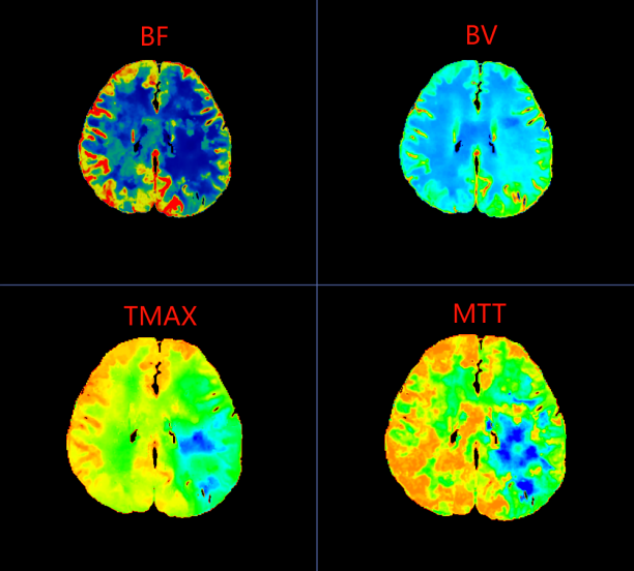

在一脉阳光辽宁影像中心,44岁的李女士(化名)带着持续了40余天的头晕与头痛,完成了一次看似平常却至关重要的检查——脑灌注CTP扫描。图像清晰显示:她左侧大脑中动脉供血区存在明显的低灌注区域,平均通过时间显著延长,脑血流量下降。

在脑梗死真正形成之前,大脑其实已经历一系列血流代偿与失代偿的过程。CTP(CT脑灌注成像)正是一种能够可视化脑血流动力学状态的前沿影像技术。它不仅能显示血管结构,更能精准评估脑组织的血流速度、血流量与血流通过时间,从而在患者尚未出现典型脑梗死症状时,就捕捉到脑灌注异常的“蛛丝马迹”。

李女士的CTP图像中,左侧大脑中动脉供血区呈现的“低灌注”表现,正是脑血流代偿机制开始崩溃的标志。这种梗死前的影像预警,为临床实施超早期干预——如强化抗血小板治疗、控制血压、改善脑灌注等——提供了至关重要的依据,从而有可能阻断病情进展,避免梗死发生。